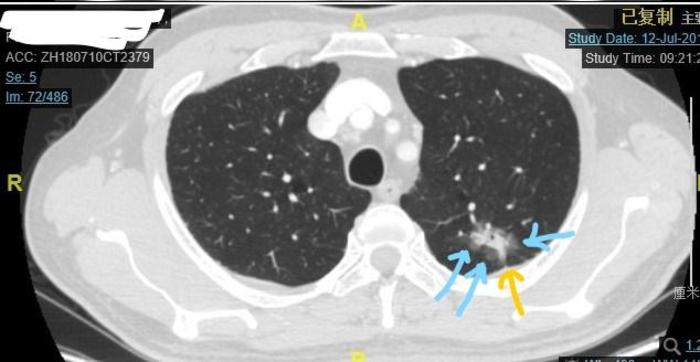

病例4荷包蛋型

结节中心的白色成分,就是这个混合磨玻璃结节的实性成分。可见实性成分比例大约15%左右。这个磨玻璃结节形状类似一个煎好的荷包蛋。结节的左侧有好几根小血管进入结节。

病理也是浸润性腺癌。有20%的亚型是乳头型,恶性度较高。当然这个患者的实性成分比例低于25%,比实性成分比例高于25%的磨玻璃结节要好一些。